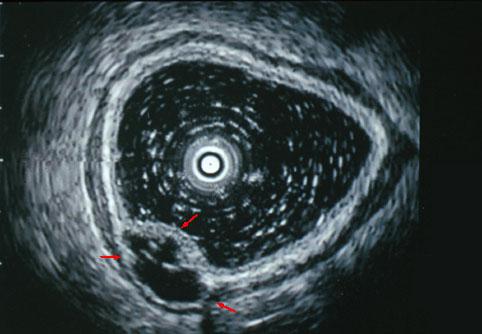

X선, 내시경, 초음파, CT, CT colonoscopy에서 묘출된 S상결장의 림프관종(큐슈우대학 G-I회 Dr.가와모토 제공)

[Image-ID:3018]

양성 비상피성종양/림프관종

대장/S상

초음파

10~14